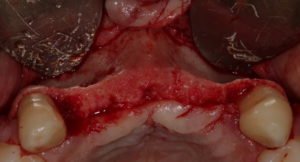

Paciente procurou a área de CBMF da Unicamp com a pré-maxila edêntula (Figuras 1 e 2) e foi submetido à técnica Screw Tent Poleutilizando os parafusos da linha Orth – Implacil de Bortolli (Figura 3). Do lado esquerdo da pré-maxila foram instalados três parafusos que apresentavam roscas em toda superfície, enquanto que do lado direito foram instalados três parafusos que não apresentam roscas no terço cervical (Figuras 4 e 5). Biomaterial associado com PRF (Stick Bone) foi adequadamente acomodado na região entre os parafusos e recoberto por membranas de PRF (Figuras 6 e 7). Uma sutura livre de tensão foi realizada para finalizar o procedimento cirúrgico (Figura 8).

figuras 4 e 5